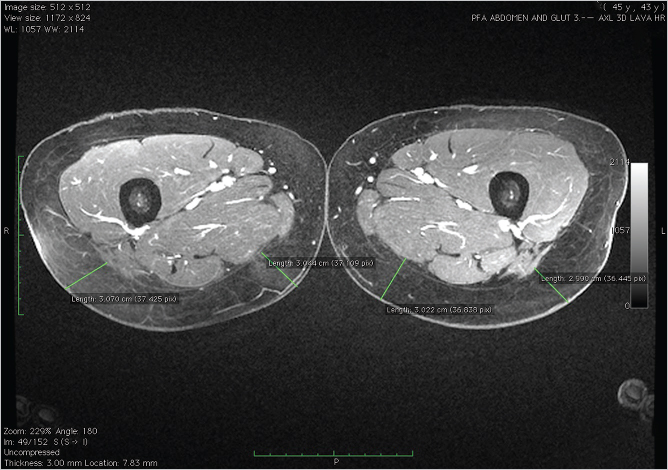

The proximal femoral artery gives rise to the profunda femoris system supplying branches to the adductor muscle group of the thigh as well as the overlying skin. Cadaver injection studies and computed tomography (CT) angiography demonstrate that the dominant blood supply to the posterior thigh arises from posterior perforators emerging from the profunda femoris artery (▶Fig. 58.2).

With the midline and inferior gluteal crease as reference points, the largest, most well-placed perforators with the longest vascular pedicle can be identified. In this image, the best perforators have been identified as R3 and L1 (▶Fig. 58.3).

Prior to surgery each of our patients undergoes a magnetic resonance (MR) or computed tomography (CT) angiogram preoperatively to determine perforator size and intraoperative course. MR or CT angiography (MRA or CTA) of the pelvis and thigh with contrast is performed in the supine position. Preoperative imaging with MRA or CTA defines the intramuscular course of perforators prior to the flap elevation. This facilitates accurate identification of the size, location, and pathway of target perforators. With the midline and inferior gluteal crease as reference points, the perforators with the longest vascular pedicle are identified (▶Fig. 58.2). The most appropriate vessel is the medial perforator closest to the inferior gluteal crease and just posterior to the gracilis muscle for ease of dissection in the supine/frog-leg position. Three-dimensional MRA reconstruction allows visualization of the perforators prior to marking (▶Fig. 58.3).